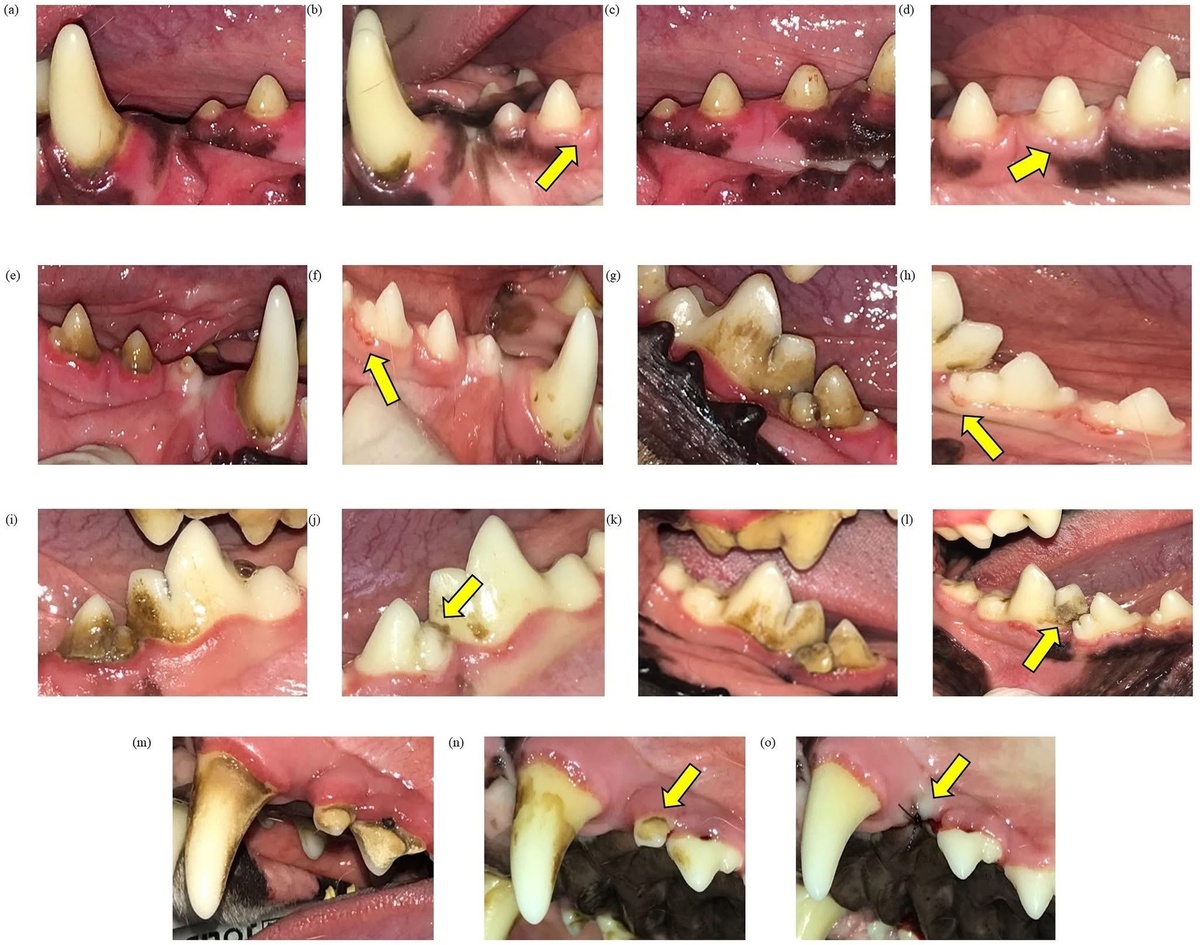

В 2020 году группа бразильских исследователей (Pinto и соавт., PLoS ONE) провела одно из наиболее детальных исследований на эту тему. В эксперименте участвовали двенадцать взрослых биглей, разделённых на две группы: одна получала плотные говяжьи кости (кортикальные), другая — более мягкие губчатые.

Собаки жевали кости ежедневно в течение двух недель. Исследователи регулярно фотографировали и рентгенографировали зубы, оценивая количество зубного камня, состояние эмали, корней и дёсен.

Результаты оказались впечатляющими. Уже через три дня зубной камень практически полностью исчез с премоляров и моляров — именно этими зубами собаки чаще всего жуют. В среднем снижение покрытия зубов камнем достигло около 90%. Также отмечалось уменьшение воспаления дёсен.

Важно, что серьёзных повреждений зубов, трещин, переломов или желудочно-кишечных осложнений не наблюдалось. Однако у нескольких собак, которым давали более мягкие губчатые кости, появились лёгкие повреждения дёсен и небольшие остатки кости между зубами. Учёные связывают это с тем, что собаки получали новые куски костей ежедневно без перерывов.

Авторы пришли к выводу: правильно подобранные кости могут быть эффективным и безопасным способом краткосрочного удаления зубного камня. Они рекомендуют использовать определённые типы костей, подходящие по размеру и плотности, и делать это под контролем.